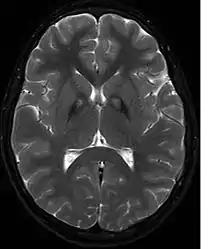

A neurological examination would show evidence of muscle rigidity; weakness; and abnormal postures, movements, and tremors. If other family members are also affected, this may help determine the diagnosis. Genetic tests can confirm an abnormal gene causing the disease. However, this test is not yet widely available. Other movement disorders and diseases must be ruled out. Individuals exhibiting any of the above listed symptoms are often tested using MRI (Magnetic Resonance Imaging) for a number of neuro-related disorders. An MRI usually shows iron deposits in the basal ganglia. Development of diagnostic criteria continues in the hope of further separating PKAN from other forms of neurodegenerative diseases featuring NBIA.

Microscopic features of PKAN include high levels of iron in the globus pallidus and the pars reticulata of substantia nigra, evident as a characteristic rust-brown discoloration[7] in a pattern called the eye-of-the-tiger sign;[8] lipofuscin and neuromelanin concentrated in the iron-accumulating areas; oval, nonnucleated structures representing swollen axons whose cytoplasm swells with vacuoles, referred to as spheroids, axon schollen, or neuroaxonal dystrophy; and Lewy bodies.[7]

Diagnosis of PKAN hit a milestone with the availability of MRIs, as well as the in-depth descriptions of those MRIs provided by Littrup and Gebarski (1985),[14] Tanfani et al. (1987),[15] Sethi et al. (1988),[16] Angelini et al. (1992),[17] Casteels et al. (1994),[18] and Malandrini et al. (1995).[19] The gene was localized to chromosome 20p by Taylor et al. (1996) [20] who suggested that this disorder should be referred to as neurodegeneration with brain iron accumulation (NBIA1) to avoid the objectionable eponym[21] of Hallervorden-Spatz. The disease was renamed 'pantothenate kinase-associated neurodegeneration' or PKAN by Zhou et al. (2001)[3] who suggested the name to avoid misinterpretation and to better reflect the true nature of the disorder. Most recently Pellecchia et al. (2005) published a report of 16 patients affected by PKAN, confirmed by genetic analysis.[22]